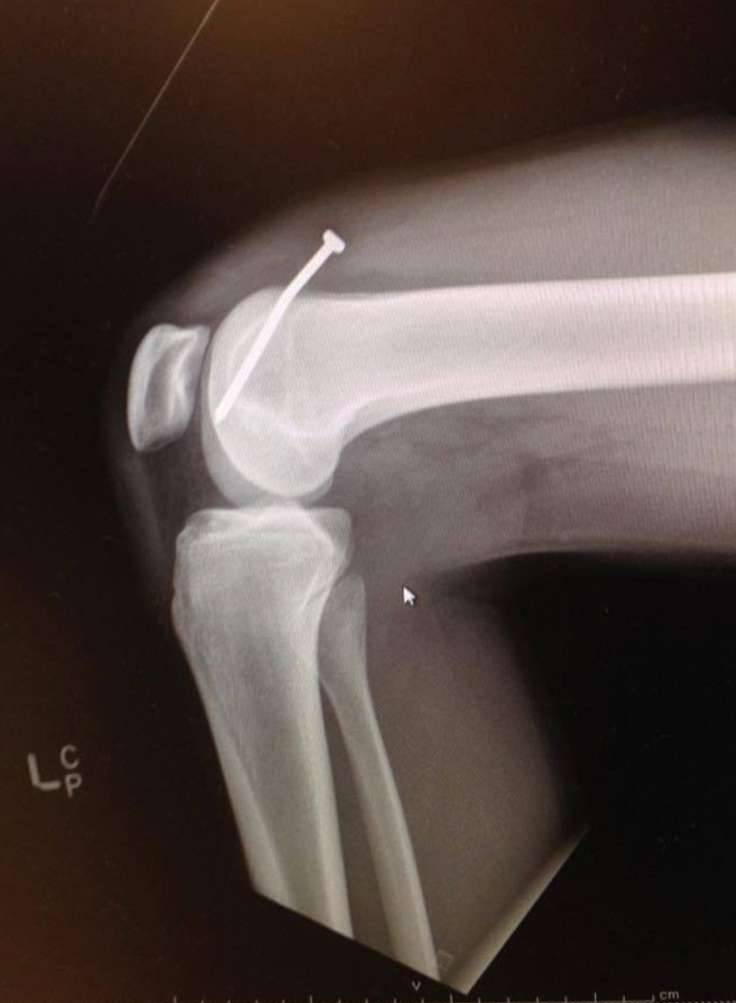

▼X光片清楚展示了一根钉子卡在膝盖内的情景…